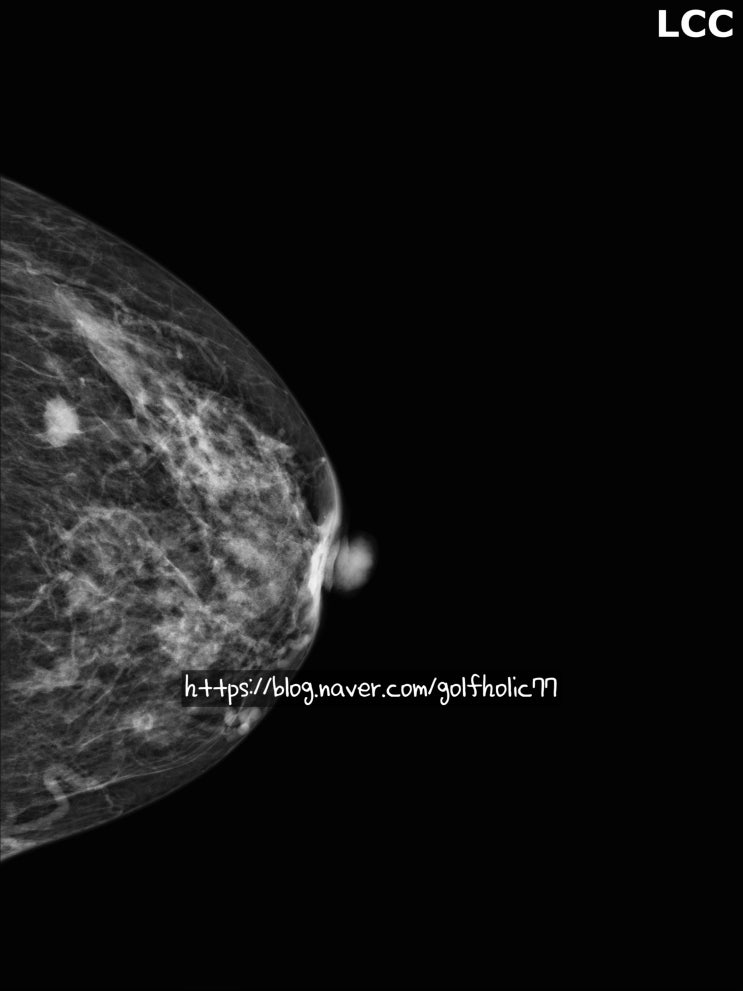

유방상피내암 0기 유방암

유방암중 상피내암이라고있습니다. 분명 유방암이지만 질병코드가 C코드가 아니라 D코드로 잡히는 제자리...

25년 첫 유방암진단

25년이 보름남짓 지난시점에 벌써 세명의 유방암을 진단하였습니다 ㅜㅜ 그만큼 유방암이 너무 많아요 흑흑...